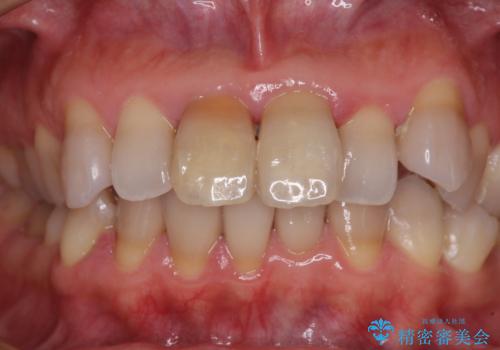

神経を取り除いた歯は、経年劣化により変色してしまいます。

前歯は審美的に、奥歯は強度的に問題が起きるため、早めにクラウンを装着することが望ましいとされています。